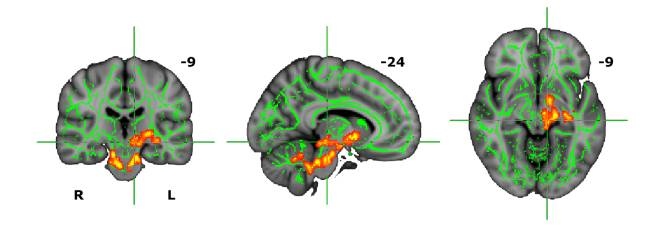

Los escaneos cerebrales, vistos desde tres niveles, muestran algunos de los efectos de la terapia hormonal en personas transgénero (femenino a masculino). La caída en la hormona estradiol se correlaciona con la disminución de la materia blanca en las regiones del tronco encefálico y el mesencéfalo (marcas rojo-amarillas). Las redes de materia blanca están marcadas en verde. (Foto: Rupert Lanzenberger)

Fue también muy interesante que los escáneres mostraran que, con anterioridad al tratamiento hormonal, la estructura del cerebro de las personas transgénero exhibía niveles que caían en el término medio entre los dos sexos.